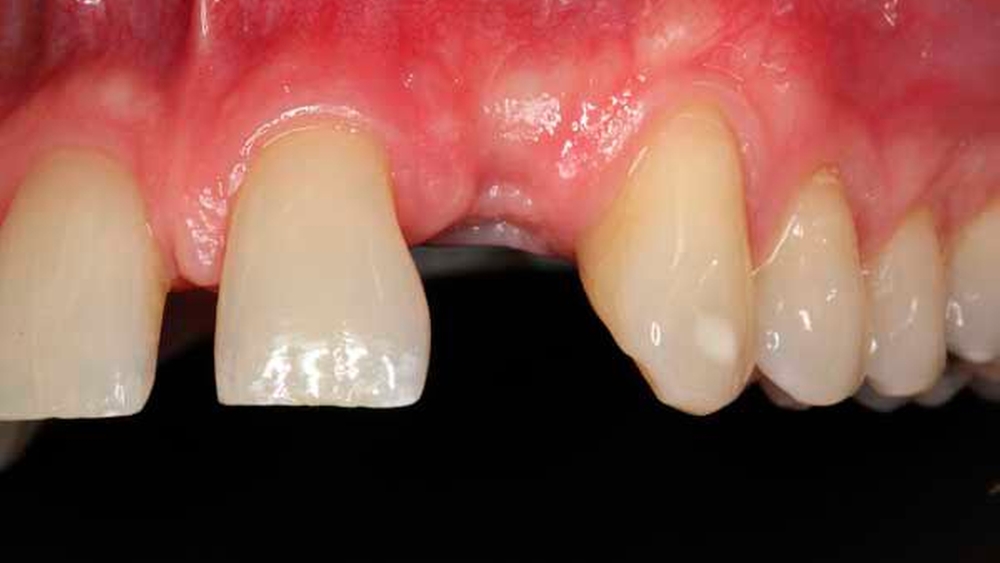

Die Allgemeinanamnese des Patienten war unauffällig. Eine Medikamenteneinnahme oder das Vorliegen von Allergien wurden verneint. Der Wunsch des Patienten war eine implantologische Lösung für den fehlenden Zahn 22 (Abbildung 1). Eine Brückenversorgung sollte, wenn möglich, vermieden werden.

Die klinische Befunderhebung ergab eine Schaltlücke regio 22. Die restlichen Zähne in Ober- und Unterkiefer zeigten keine Auffälligkeiten. Der CO2-Sensibilitätstest der Zähne 21 und 23 war positiv. Ein Diastema lag zwischen den Zähnen 11 und 21 vor (Abbildung 1). Auch Zahn 22 stand zuvor auf Lücke zu Zahn 21.